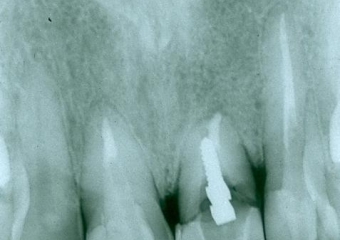

Raio x com prótese provisória fixa sobre implante

Raio x final